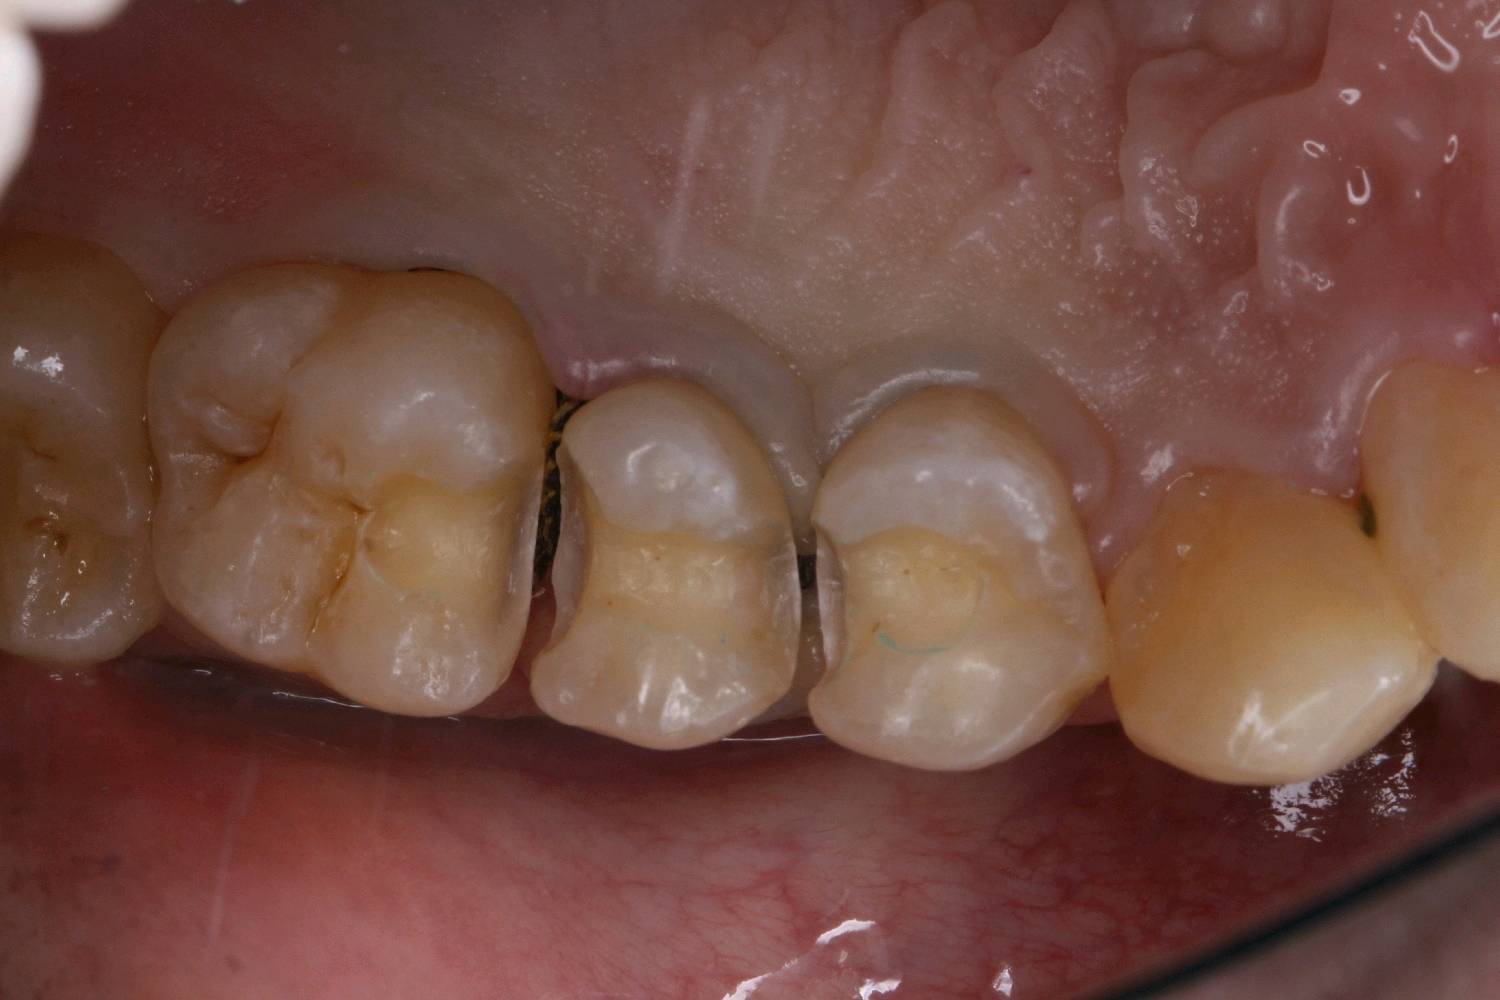

患者男24岁,自述右侧后牙食物嵌塞,无用牙线习惯。检查发现14,15,16,45,46 ,47邻颌面龋坏,探(-),扣(-),冷测正常,龋坏至牙本质中层,余无特殊。

治疗计划:嵌体修复

食物嵌塞为细菌提供了良好的滋生环境,容易导致细菌大量繁殖,产生酸性物质,从而增加蛀牙的风险。最好是用嵌体修复,能更好的恢复牙体的形态和功能。想要有一口好牙齿,做起来也不难。但是,单单口腔清洁这件小事,大多数人都没做好。你以为刷遍了牙齿的每个角落,但可能只刷了一半的牙。刷毛无法有效进入牙缝隙刷牙后仍有食物残渣等残留于牙齿邻面部位导致邻面龋坏。平时不易察觉,需要定期检查,为了更恢复邻接关系,预备制作嵌体,更好的恢复了牙体形态,增加了固位力,恢复正常的邻接关系,可以得到更好洁。基牙预备后,通过德国西诺德 CEREC ,当日完成即可佩戴,患者满意。